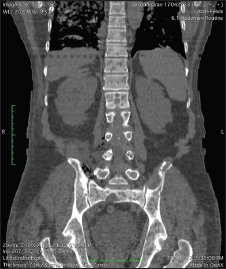

Initial blood reports showed mild anemia, high erythrocyte sedimentation rate, AKI with life-threatening hypercalcemia, high serum calcium of 17.6 mg/dl, and liver function test showing altered AG ratio. Hence, we worked up for the causes of the same. Thyroid-stimulating hormone and parathyroid hormone were low with values of 0.233 and 6.90 pg/ml, respectively. Urine microscopy showed features suggestive of urinary tract infection (UTI), and urine culture was sent which subsequently showed no growth. He also had an lower respiratory tract infection with a chest X-ray showing right-sided nonhomogeneous opacity with pleural effusion. Initially, the patient was suspected with AKI, UTI, hypercalcemia under evaluation, and right lower lobe consolidation. Initially, the patient was managed conservatively with intravenous (IV) fluids and IV antibiotics which were later shifted to higher spectrum antibiotics such as meropenem, after which, fever spikes reduced. In view of the hypercalcemia, the patient was further worked up with suspicion toward multiple myeloma. Serum electrophoresis was done, which showed M-band. X-ray skull lateral view showed multiple lytic lesions [Figure 1].

| Figure. 1 X-ray skull showing lytic lesions